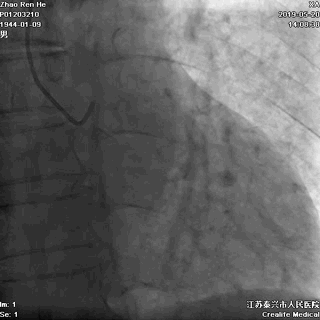

LAD发出第一对角支后即慢性闭塞

闭塞入口显示不清

闭塞出口处血管相对比较“健康”

LAD闭塞段小于20mm

LM分叉相对正常

未见提供LAD的逆向侧枝

推测LAD存在前向微孔道